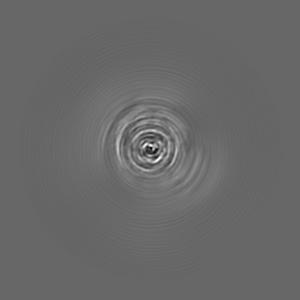

Cryo-EM structure of alpha-synuclein singlet filament from Juvenile-onset synucleinopathy

Helical reconstruction2.0 Å

Sample: Alpha-synuclein singlet filament extracted from the human brain with JOS